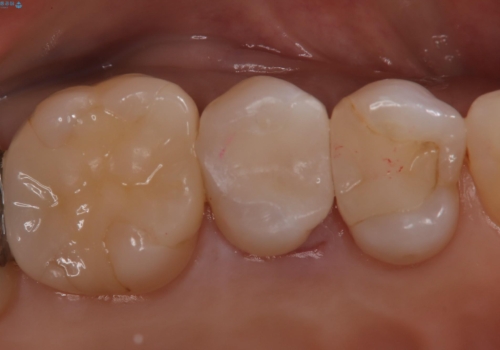

【セラミックインレー】昔治療した詰め物が外れた。

- 他院でいれたセラミックインレーが脱離して、来院されました。

新たに製作を希望されたため、当院で治療しました。

当院でのセラミックインレーの治療は、ラバーダムを使用しています。